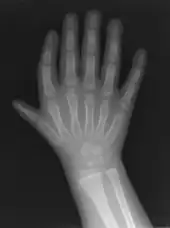

Triphalangeal thumb (TPT) is a congenital malformation where the thumb has three phalanges instead of two. The extra phalangeal bone can vary in size from that of a small pebble to a size comparable to the phalanges in non-thumb digits. The true incidence of the condition is unknown, but is estimated at 1:25,000 live births.[1] In about two-thirds of the patients with triphalangeal thumbs, there is a hereditary component.[2] Besides the three phalanges, there can also be other malformations. It was first described by Columbi in 1559.[3]

The triphalangeal thumb has a different appearance than normal thumbs. The appearance can differ widely; the thumb can be a longer thumb, it can be deviated in the radio-ulnar plane (clinodactyly), or thumb strength can be diminished. In the case of a five-fingered hand it has a finger-like appearance, with the position in the plane of the four fingers, thenar muscle deficiency, and additional length. There is often a combination with radial polydactyly.